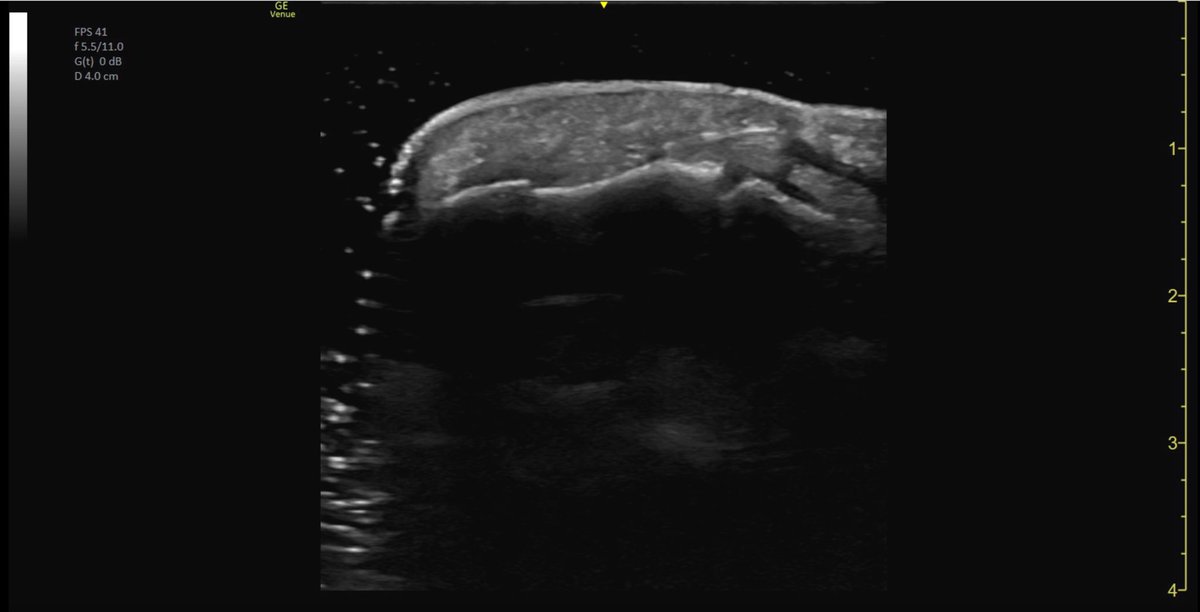

ECOGRAFÍA CLINICA OCULAR Desprendimiento de retina (mejor pronóstico para el paciente cuando la retina todavía está adherida a la mácula) #raysofgray #POCUS #ultrasound #FOAMed #MedEd #emergencymedicine #medicalstudent #resident

RESOLUTION: S: Eyeball/Globe/Small Part/Small Organ R: Mac ON Retinal Detachment (better prognosis for patient when the retina is still attached to the macula) #raysofgray #POCUS #ultrasound #FOAMed #MedEd #emergencymedicine #medicalstudent #resident